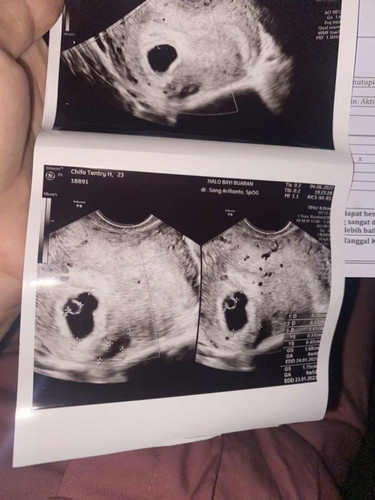

bun mau nanya dong, aku hamil 7 week, #pleasehelp apa perlu aku ke dokter ya td subuh perut aku kya kontraksi sakit banget22222 dari biasanya sampe nangis2 cuma pas aku cek alhamdulillah ngga ada flek / pendarahan, dan pas udah pagi aku bangun lagi udah ngga sakit. aku tetep harus ke dokter atau ngga ya bun? hari sabtu lalu aku usg dan hasilnya ada pendarahan dalam rahim, gimana baiknya ya? apakah aku harus ke dokter lagi sekarang?#ingintahu #firstmom

hai bun, alhamdulillah usia kandungan ku skrg 6 week dan memang lg bedrest 1 minggu ini karna sempet flex 3x tp beda2 hari (karna kecapean ada aktivitas dikit huhu). terus aku rencananya mau konsul hari minggu ini… tp minggu lalu pas aku flek kan aku udh konsul dapet penguat kandungan terus disuruhnya balik lg 2 minggu lagi, tp aku ga sabar dan pengen konsul minggu ini krn sempet flek lagi kan, menurut bunda2 konsul aja atau nunggu 2 minggu lagi? kirakira kalo usia 6 week udh bs keliatan blm ya janinnya pake usg transvaginal? krn pas 5 week itu baru kantong aja sih… terus aku jg bingung kapan aku harus cek darah spt tokso, darah lengkap, dan lain2? perlukah aku minta ke dokternya? atau tunggu kapan ya bun untuk cek? soalnya aku feeling Hb ku rendah krn ketika bangun dr tmpt tidur mataku lgsg gelap banget dan pusing dirumah aku jg punya kucingggg niii kirakira ngaruh gak ya bun? hehehe maaf ya bun banyak pertanyaannya… soalnya ini kehamilan pertama kuu & masih was was gitu jd banyak paniknya hihi🥰 harap maklum yaaa terimakasih semuanya #firstmom #ingintahu